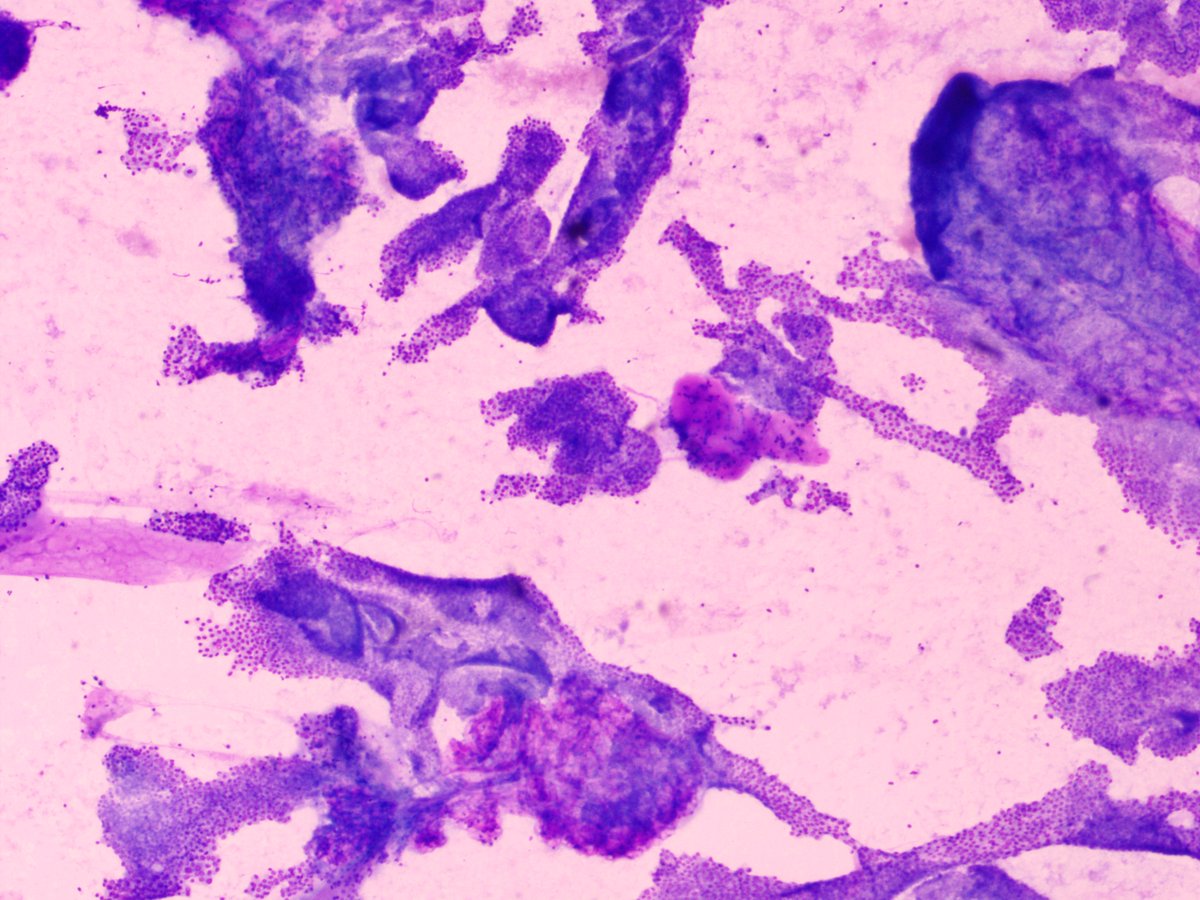

47/F swelling submandibular region #cytopath #pathtwitter @pepeheffernan @vi_monappa @kriyer68 @kr_abhisek

9

15

65